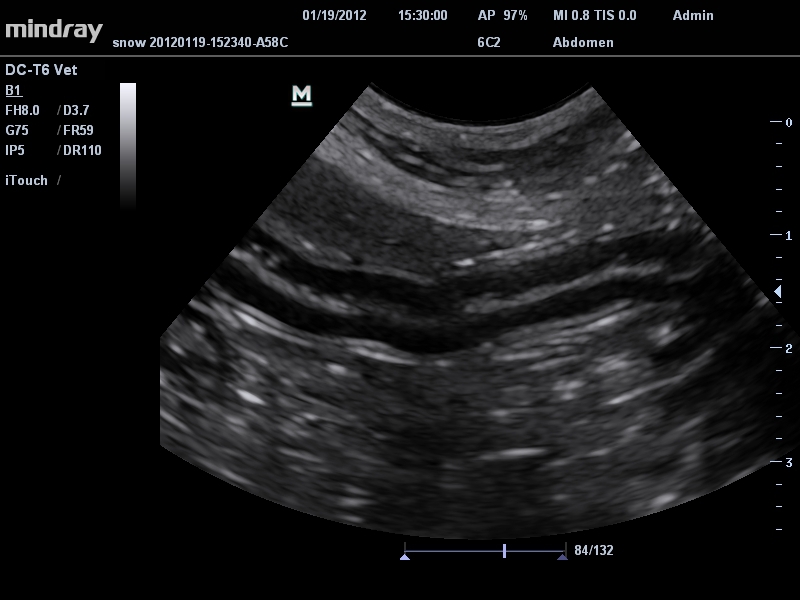

• Микроконвексный датчик Mindray 6C2

Ветеринария:

Да